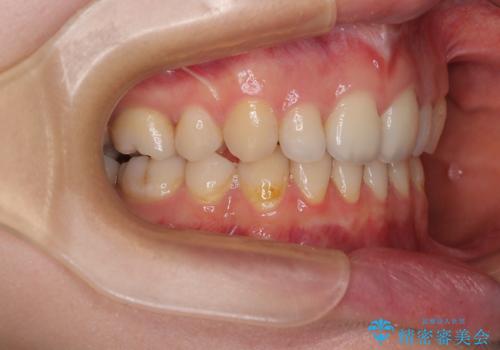

乳歯を残し、欠損部位のスペースを適正な幅に拡大し、インプラント補綴治療により歯列を整える治療も考えられましたが、ご本人から飛び出している前歯をどうしても引っ込めたいとの要望があったため、残存乳歯ならびに上顎左右第二小臼歯を抜歯して、歯列を整えることとしました。

甚大な咬合力に抵抗して過蓋咬合を改善する必要があり、更には口元が引っ込みすぎることがないように仕上げていく必要もあったため、治療期間は3年を超えましたが、当初計画通りの仕上がりで治療を終えることができました。